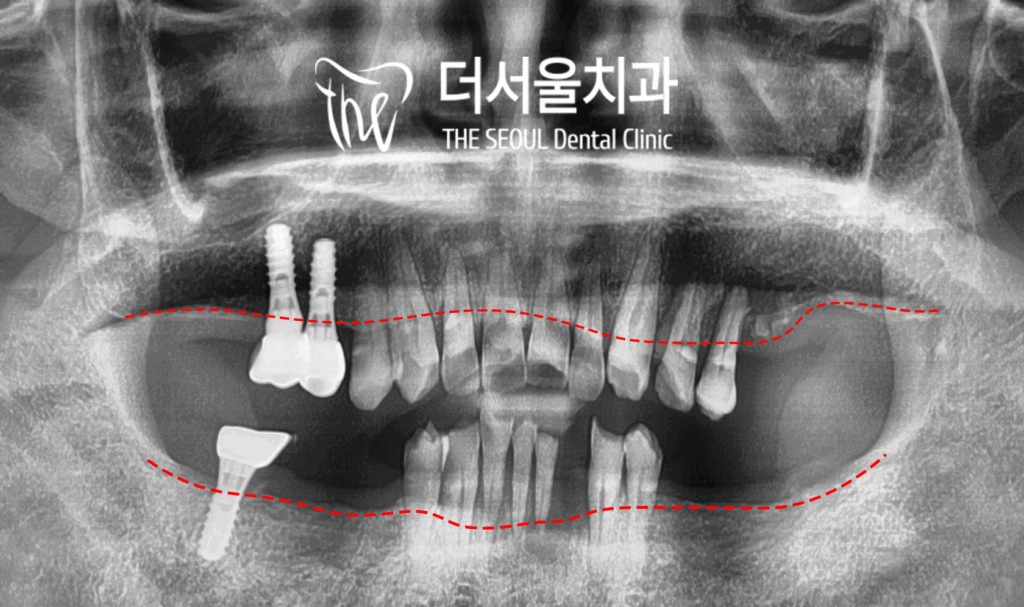

【 초진 내용 】

이 분의 엑스레이를 보면, 치조골이 많이

아래로 내려가 있는 것을 보실 수 있습니다.

즉, 골 퇴축 현상이 진행이 되고 있는건데

치아들이 상실됨에 따라

주위를 감싸고 있던 잇몸뼈들이

서서히 녹고 있는 상황입니다.

파란색으로 표기를 한 곳이, 본래 있어야 될

Bone level 인데, 빨간색의 높이만큼

이런 점으로 보아, 이 분은 상당히

늦게 치과에 찾아오시게 된 거죠.